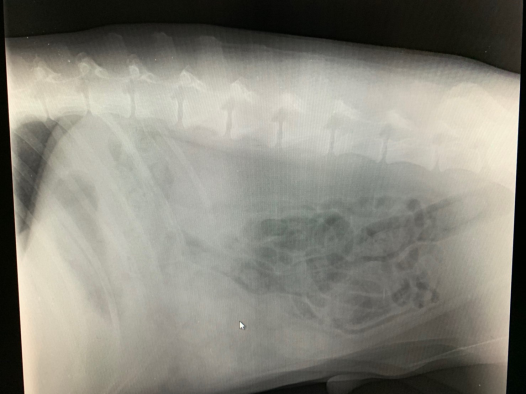

レントゲンで消化管が下腹部によっています。